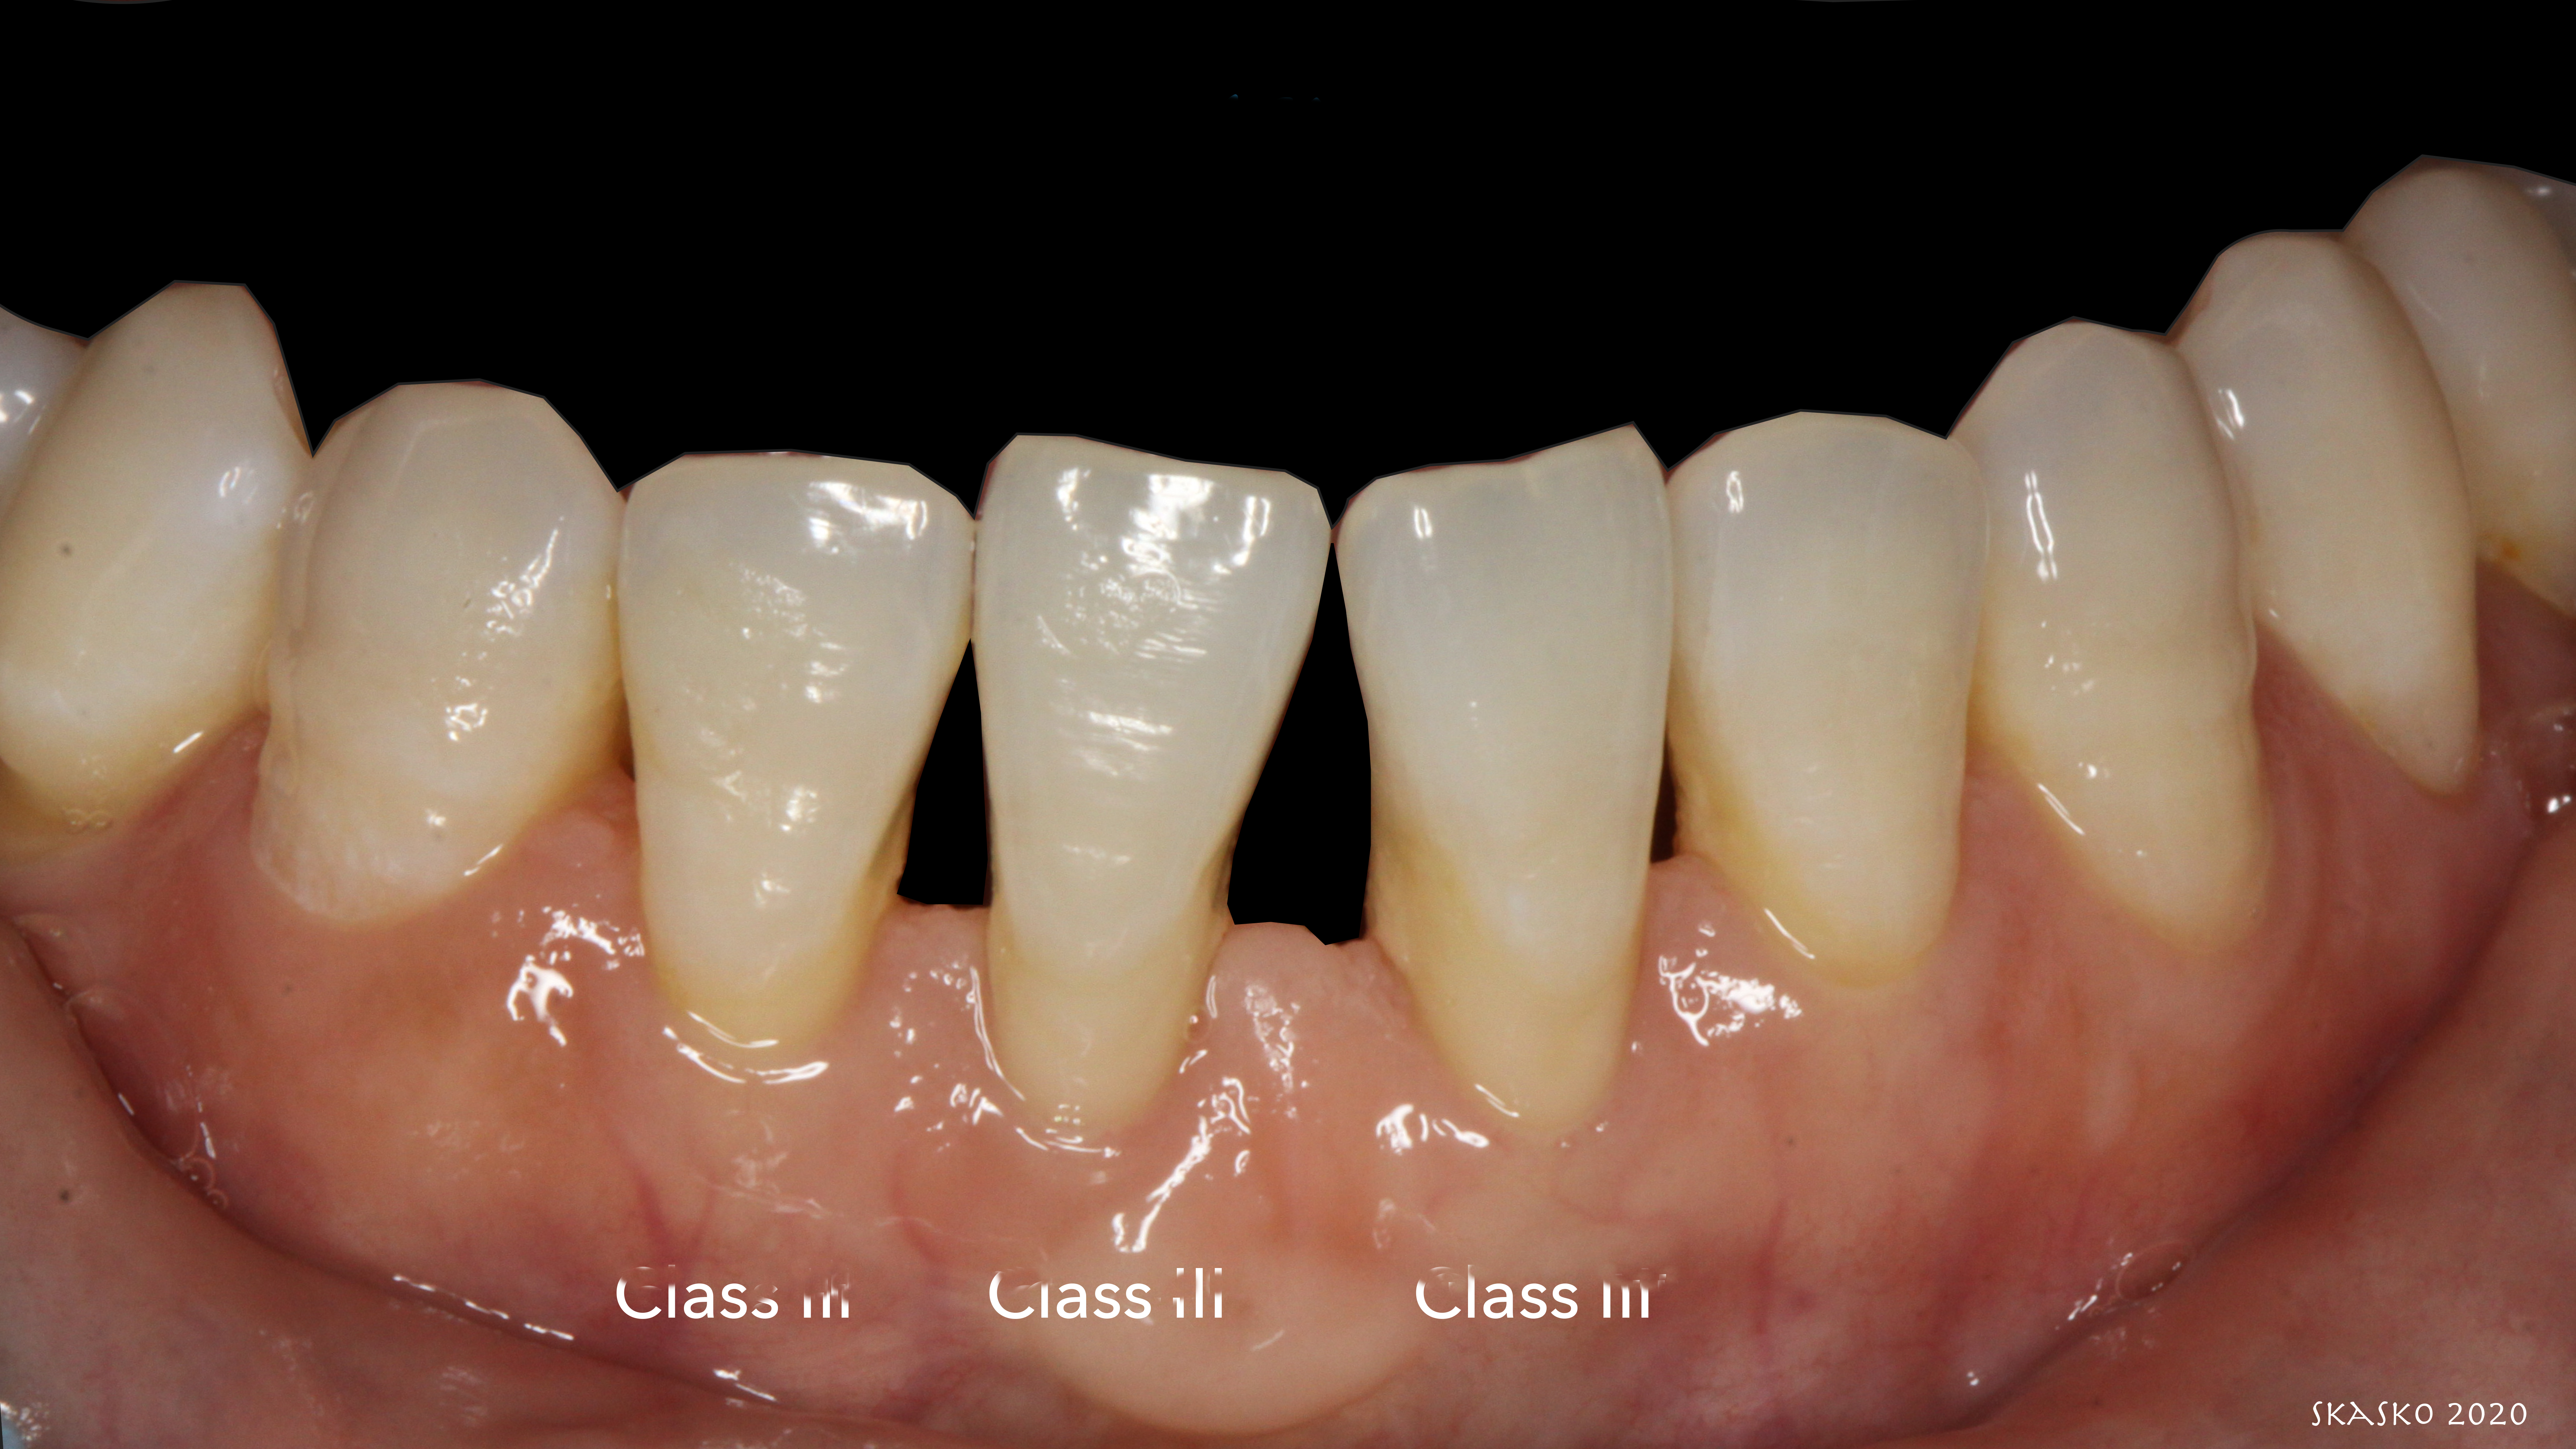

A determination of parameters for patient selection requires an examination of the classes of marginal tissue recession as defined by Dr. P.D. Miller. A conservative approach to treating Class III and Class IV recession defects, per Miller, is possible utilizing a combination of pink and white Giomer Technology restorative materials. A Miller Class III features marginal tissue recession that extends to or beyond the mucogingival junction, with periodontal attachment loss in the interdental area or malpositioning of teeth, and a Miller Class IV features marginal tissue recession that extends to or beyond the mucogingival junction, with severe bone or soft tissue loss in the interdental area and/or malpositioning of teeth1 (Figure 1). Recommended parameters for proper patient selection relating to this type of procedure generally include the existence of Class III and/or Class IV recession.

Patient "Jen," age 42, presented with Class III defects (Figure 7) and had previously had a free gingival graft between tooth Nos. 24 and 25. Treatment options were porcelain veneers; porcelain crowns/porcelain bridge after splinting or with removal of tooth Nos. 24 and 25 and pontics; removal of mandibular central mandibular incisors with implant placements (variable placements and restorative options); and composite bonding with or without periodontal splinting.

Fig 1. Miller classification of marginal tissue recession.

Fig 7. Patient presents with Miller Class III defects.